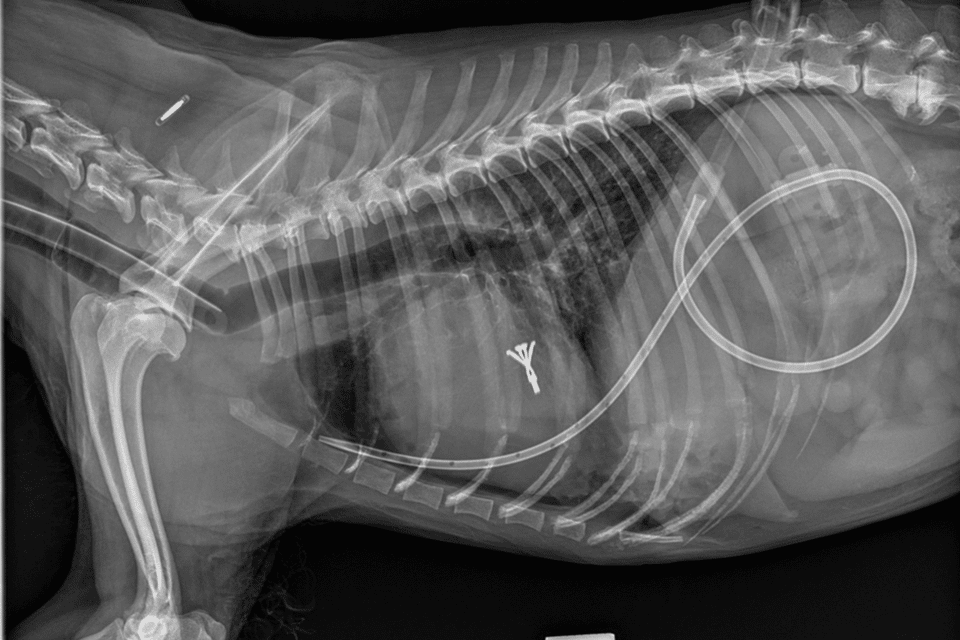

“Instead of open-heart surgery, I make a small opening from the side of the chest and introduce a V-Clamp device (canine valve clamp) through a catheter into the dog’s beating heart, guided by video X-rays and a 3D heart scan,” Dr Chow, 36, explained.

Inspired by the MitraClip device for humans, the V-Clamp – approximately 8mm in length – clips the leaky mitral valve leaflets together, reducing the backflow of blood into the heart chambers and improving its function.

The entire operation took about 90 minutes – one-third of which was used to position and deploy the clamp, Dr Chow said.

Dingding was able to go home after being warded and monitored at Atlas Vet for just two nights. Today, the maltipoo is healthy and does not need the medication to manage her heart.